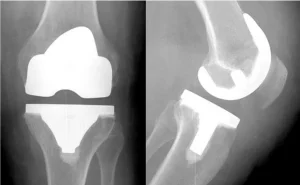

Prótese

Técnica utilizada para substituir a articulação danificada por uma prótese, ou seja, um implante em metal e polietileno. Esse procedimento é mais indicado quando o dano a cartilagem for irrecuperável, muito extenso e em pessoas com idade acima de 40 a 50 anos. Existem próteses de joelho parciais onde é substituído apenas um compartimento, ou seja, quando o desgaste é limitado apenas uma parte do joelho e próteses totais onde realiza a troca de toda a articulação (fêmur e tíbia).